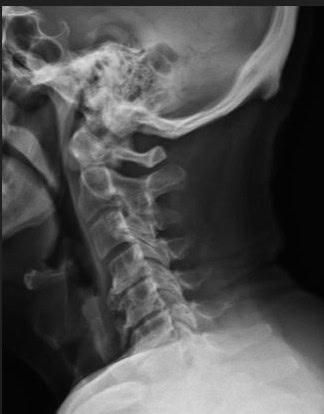

Post Scan